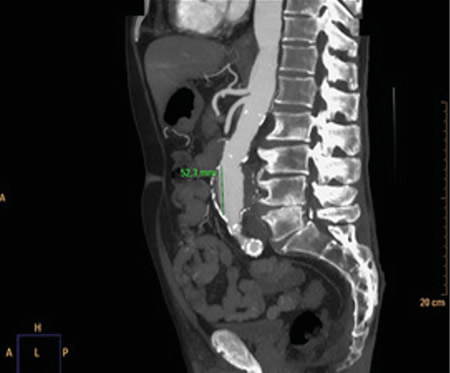

Respecto a las pruebas complementarias, en la analítica sanguínea, se halla una PCR de 39,1 mg/l, leucocitosis de 21.300/mm3, con 88 % de neutrófilos, y una hemoglobina de 10,5 g/dl. En la radiografía pélvica no se evidencian hallazgos patológicos. Debido a la hipotensión, se decide realizar un TC abdominal (Figuras 1 y 2), en el que se objetiva un aneurisma de aorta infrarrenal roto, con diámetro de 50 x 52 x 48 milímetros, a 50 mm de arteria renal derecha y a 65 mm de arteria renal izquierda, craneal a la bifurcación ilíaca. Asimismo, se aprecia un hematoma retroperitoneal en contexto de sangrado en parte posterior de la aorta, que infiltra el músculo psoas ilíaco izquierdo, justificando la clínica de coxalgia con irradiación izquierda. Se contacta con cirugía vascular, interviniéndose de forma urgente, con buena evolución posterior.

Fig. 1. TC coronal de aneurisma de aorta abdominal.

Fig. 2. TC transversal de aneurisma de aorta abdominal.